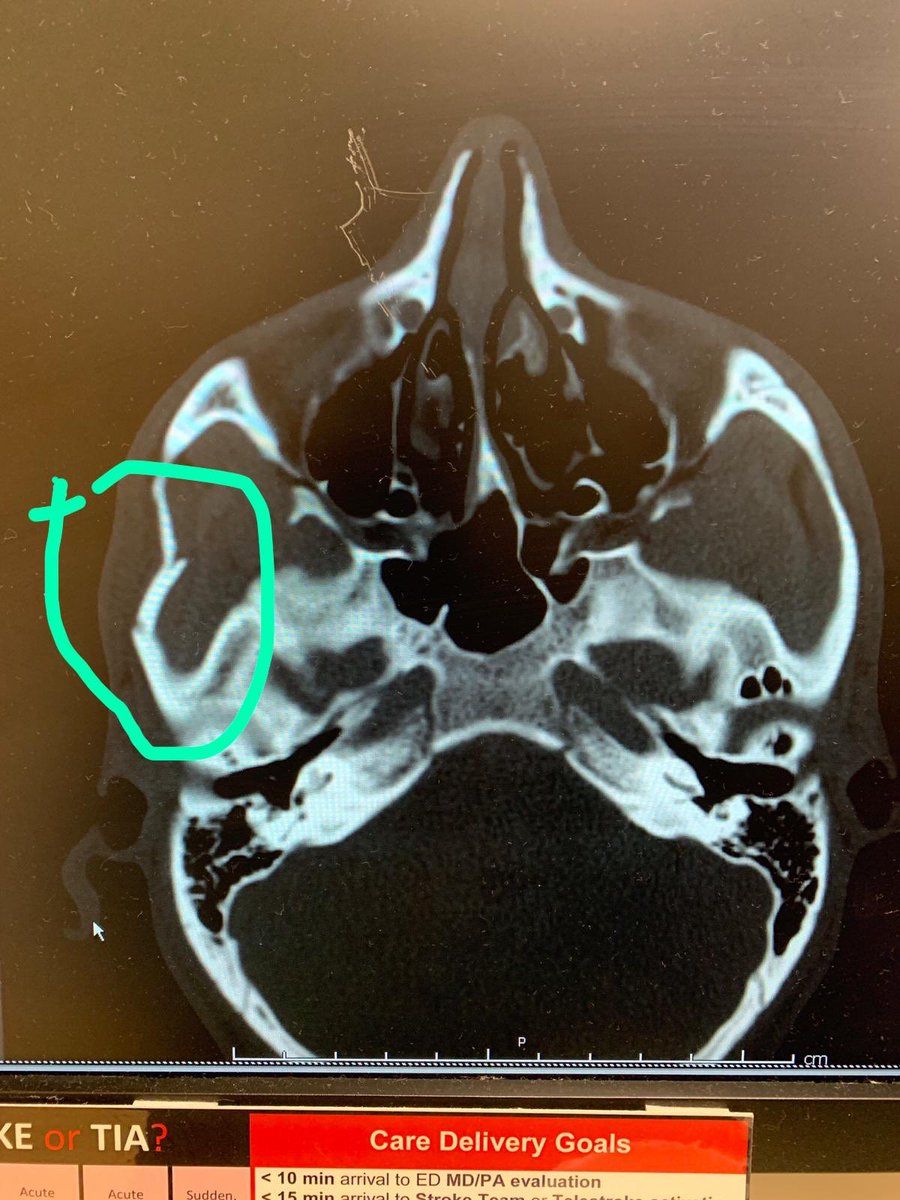

Kết quả chụp chiếu cho thấy El-Munir đã bị một vết nứt ở hộp sọ và nhiều khả năng sẽ cần đến một cuộc phẫu thuật để chữa trị vết thương khá nghiêm trọng này.

| Hình ảnh chấn thương kinh hoàng của hậu vệ Mohamed El-Munir |